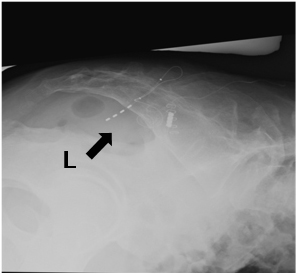

リード留置後の透視画像

側面像   正面像

L: Lead

画像提供:自治医科大学 味村 俊樹 先生